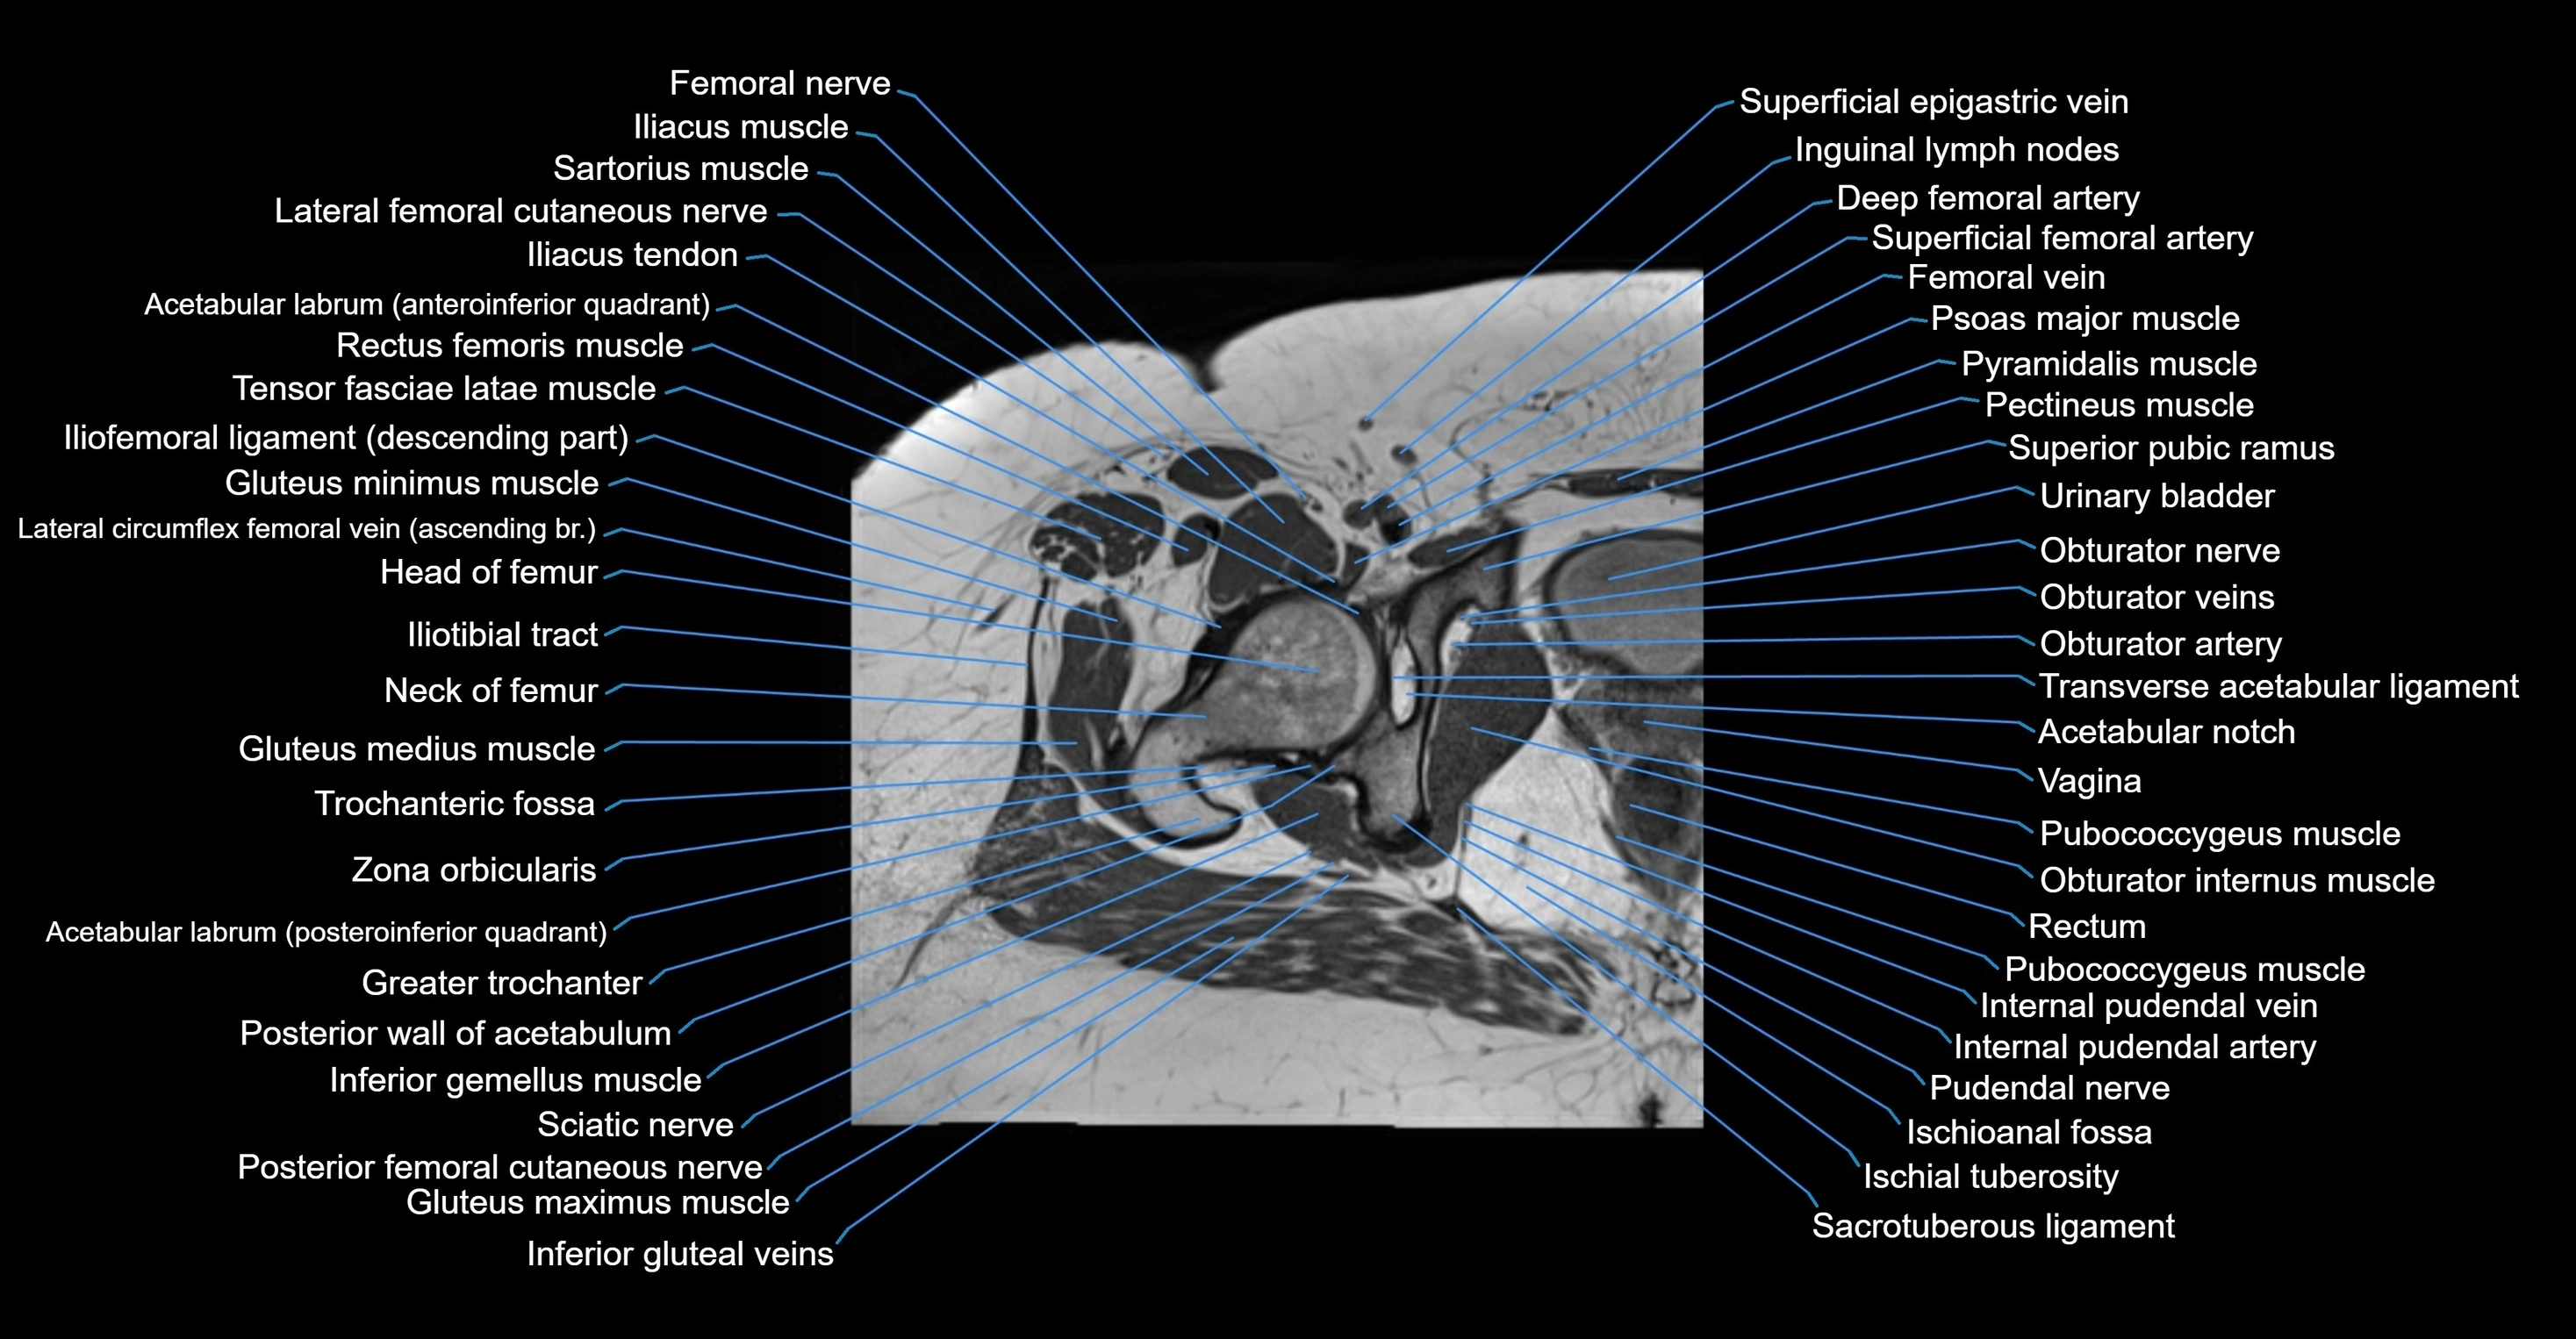

- Head of femur

- Neck of femur

- Trochanteric fossa

- Transverse acetabular ligament

- Zona orbicularis ligament

- Ischioanal fossa

- Ischial tuberosity

- Pudendal nerve